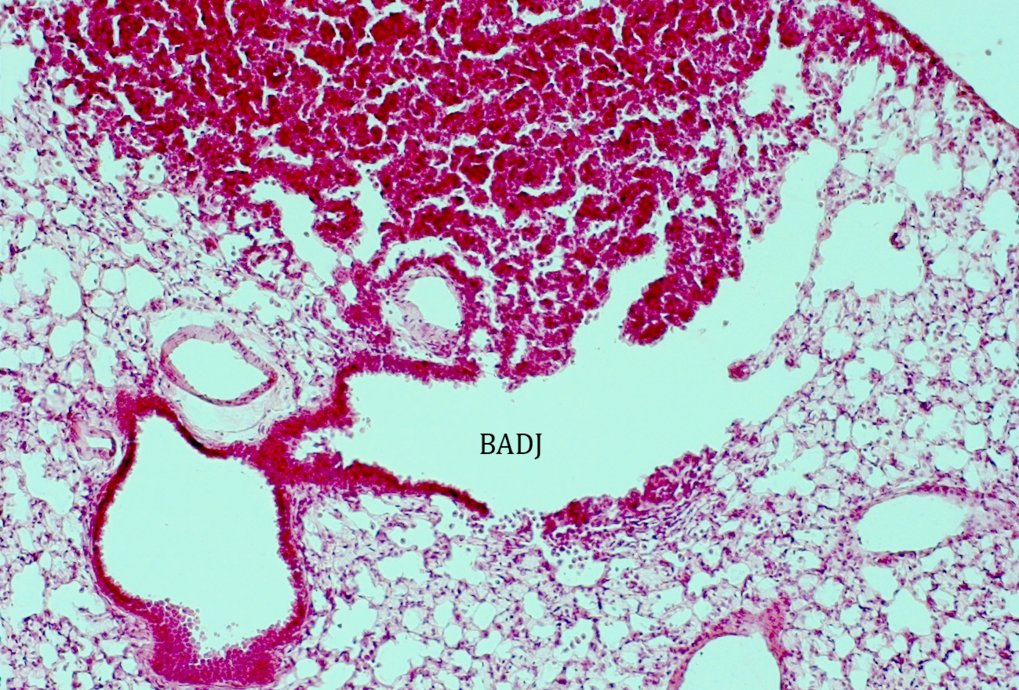

Neoplastic lesions frequently arise in the vicinity of bronchioalveolar duct junctions (BADJs).

Hematoxylin and eosin staining of lung tissue derived from an animal carrying a “latent Kras allele”, capable of spontaneous somatic activation of oncogenic Kras (KrasLA2).